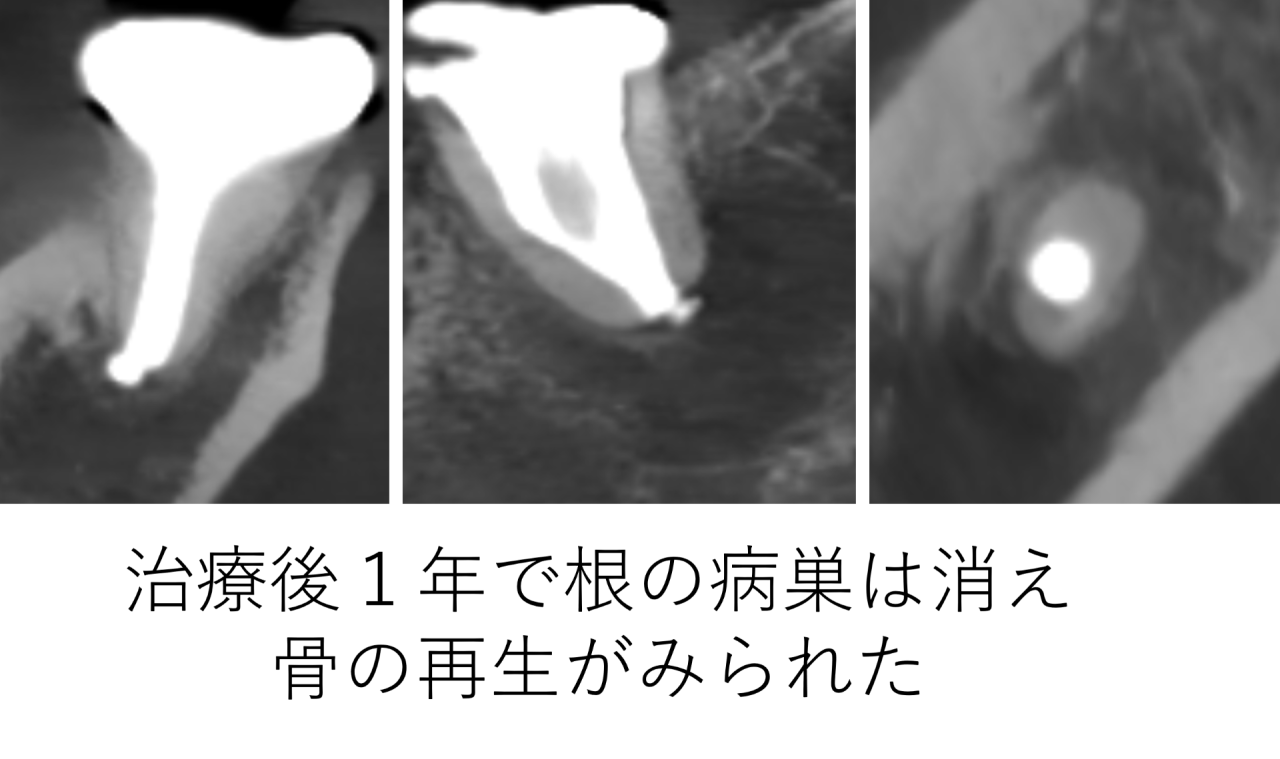

1年後、大きな根尖病巣は消え骨の再生が確認できました

そして1年後にCTで確認したところ、治療前に大きく黒く写っていた根の先の病巣は改善し、骨の再生が確認できました。

しかし、精密な根管治療を行うことで、1年後には病巣の改善と骨の再生が確認できました。